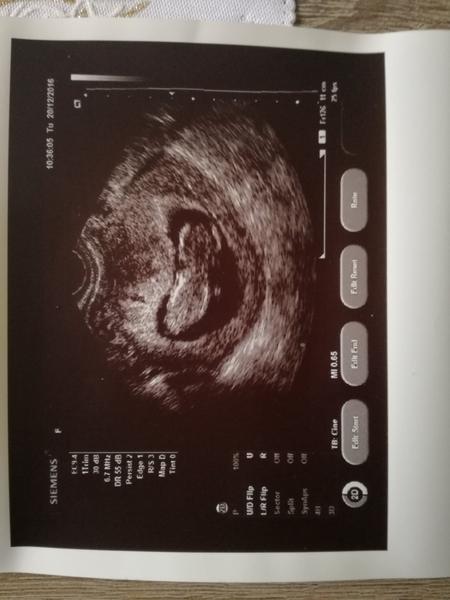

Ahojte, tak uz mam poradnu zasebou. Vsetko je v poriadku. Som 12tt+1 podla USG. Malicke je 56,1mm velke a veeelmi aktivme 😀 Odbery mi budu robit az 18.1. a vtedy dostanem aj teh.knizku. Mam len trocha vyssi tlak preto mi dal magne b6.